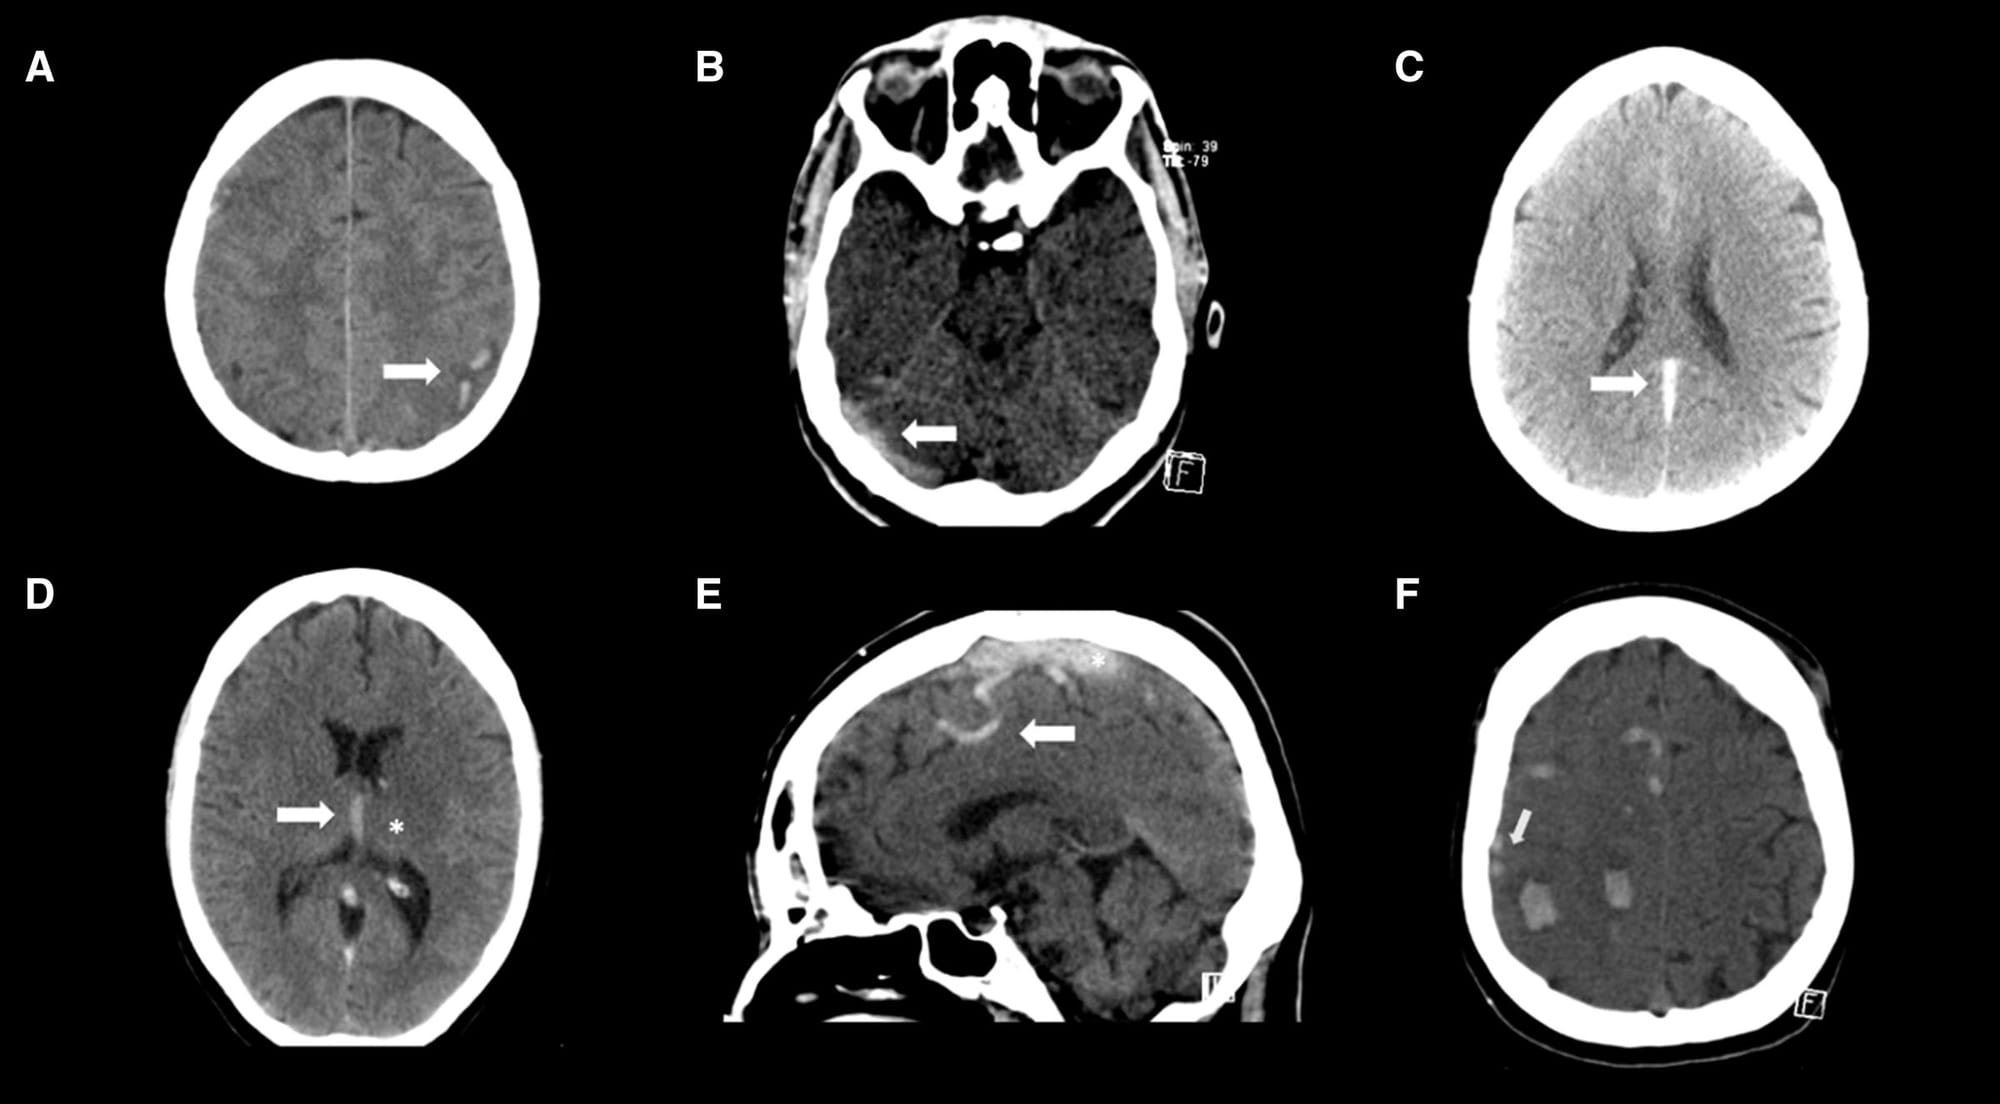

In the Emergency Department, a non-con CT/CT venogram revealed the diagnosis: extensive cerebral venous sinus thrombosis. The thrombosis involved the straight sinus, the left transverse sinus, the sigmoid sinus, and the proximal left internal cerebral vein. Routine blood tests were normal, and a thrombophilia screen—covering JAK2, PNH, Factor V Leiden, and Protein S—was also normal. He tested negative for COVID. CT abdomen and pelvis was also normal.

- Imaging: A normal non-contrast CT does not rule out the diagnosis of CVT. MR venography (MRV) or CT venography (CTV) are the optimal tests.